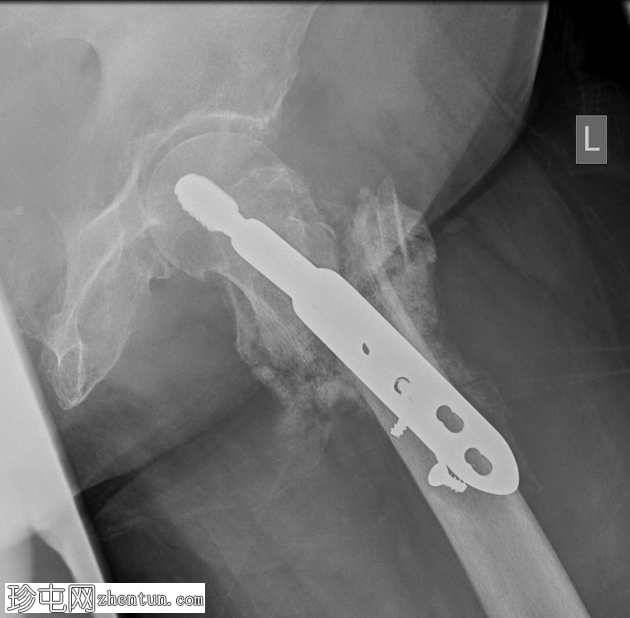

X线片

侧位片

最下方三枚螺钉发生骨折,螺钉头移位。远端钢板松动。骨膜广泛钙化,股骨颈骨折仍清晰可见。